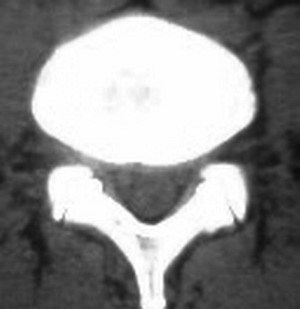

以下是引用fumaogui在2007-4-7 10:58:00的发言:[br]右侧腰4-5及骶1水平右侧神经根较对侧增粗,建议做mri排除一下神经源性肿瘤.

以下是引用zjzjr在2007-4-7 11:00:00的发言:[br]考虑腰4--5椎间盘突出长期压迫刺激致腰5神经根水肿,建议mr除外占位性病变。